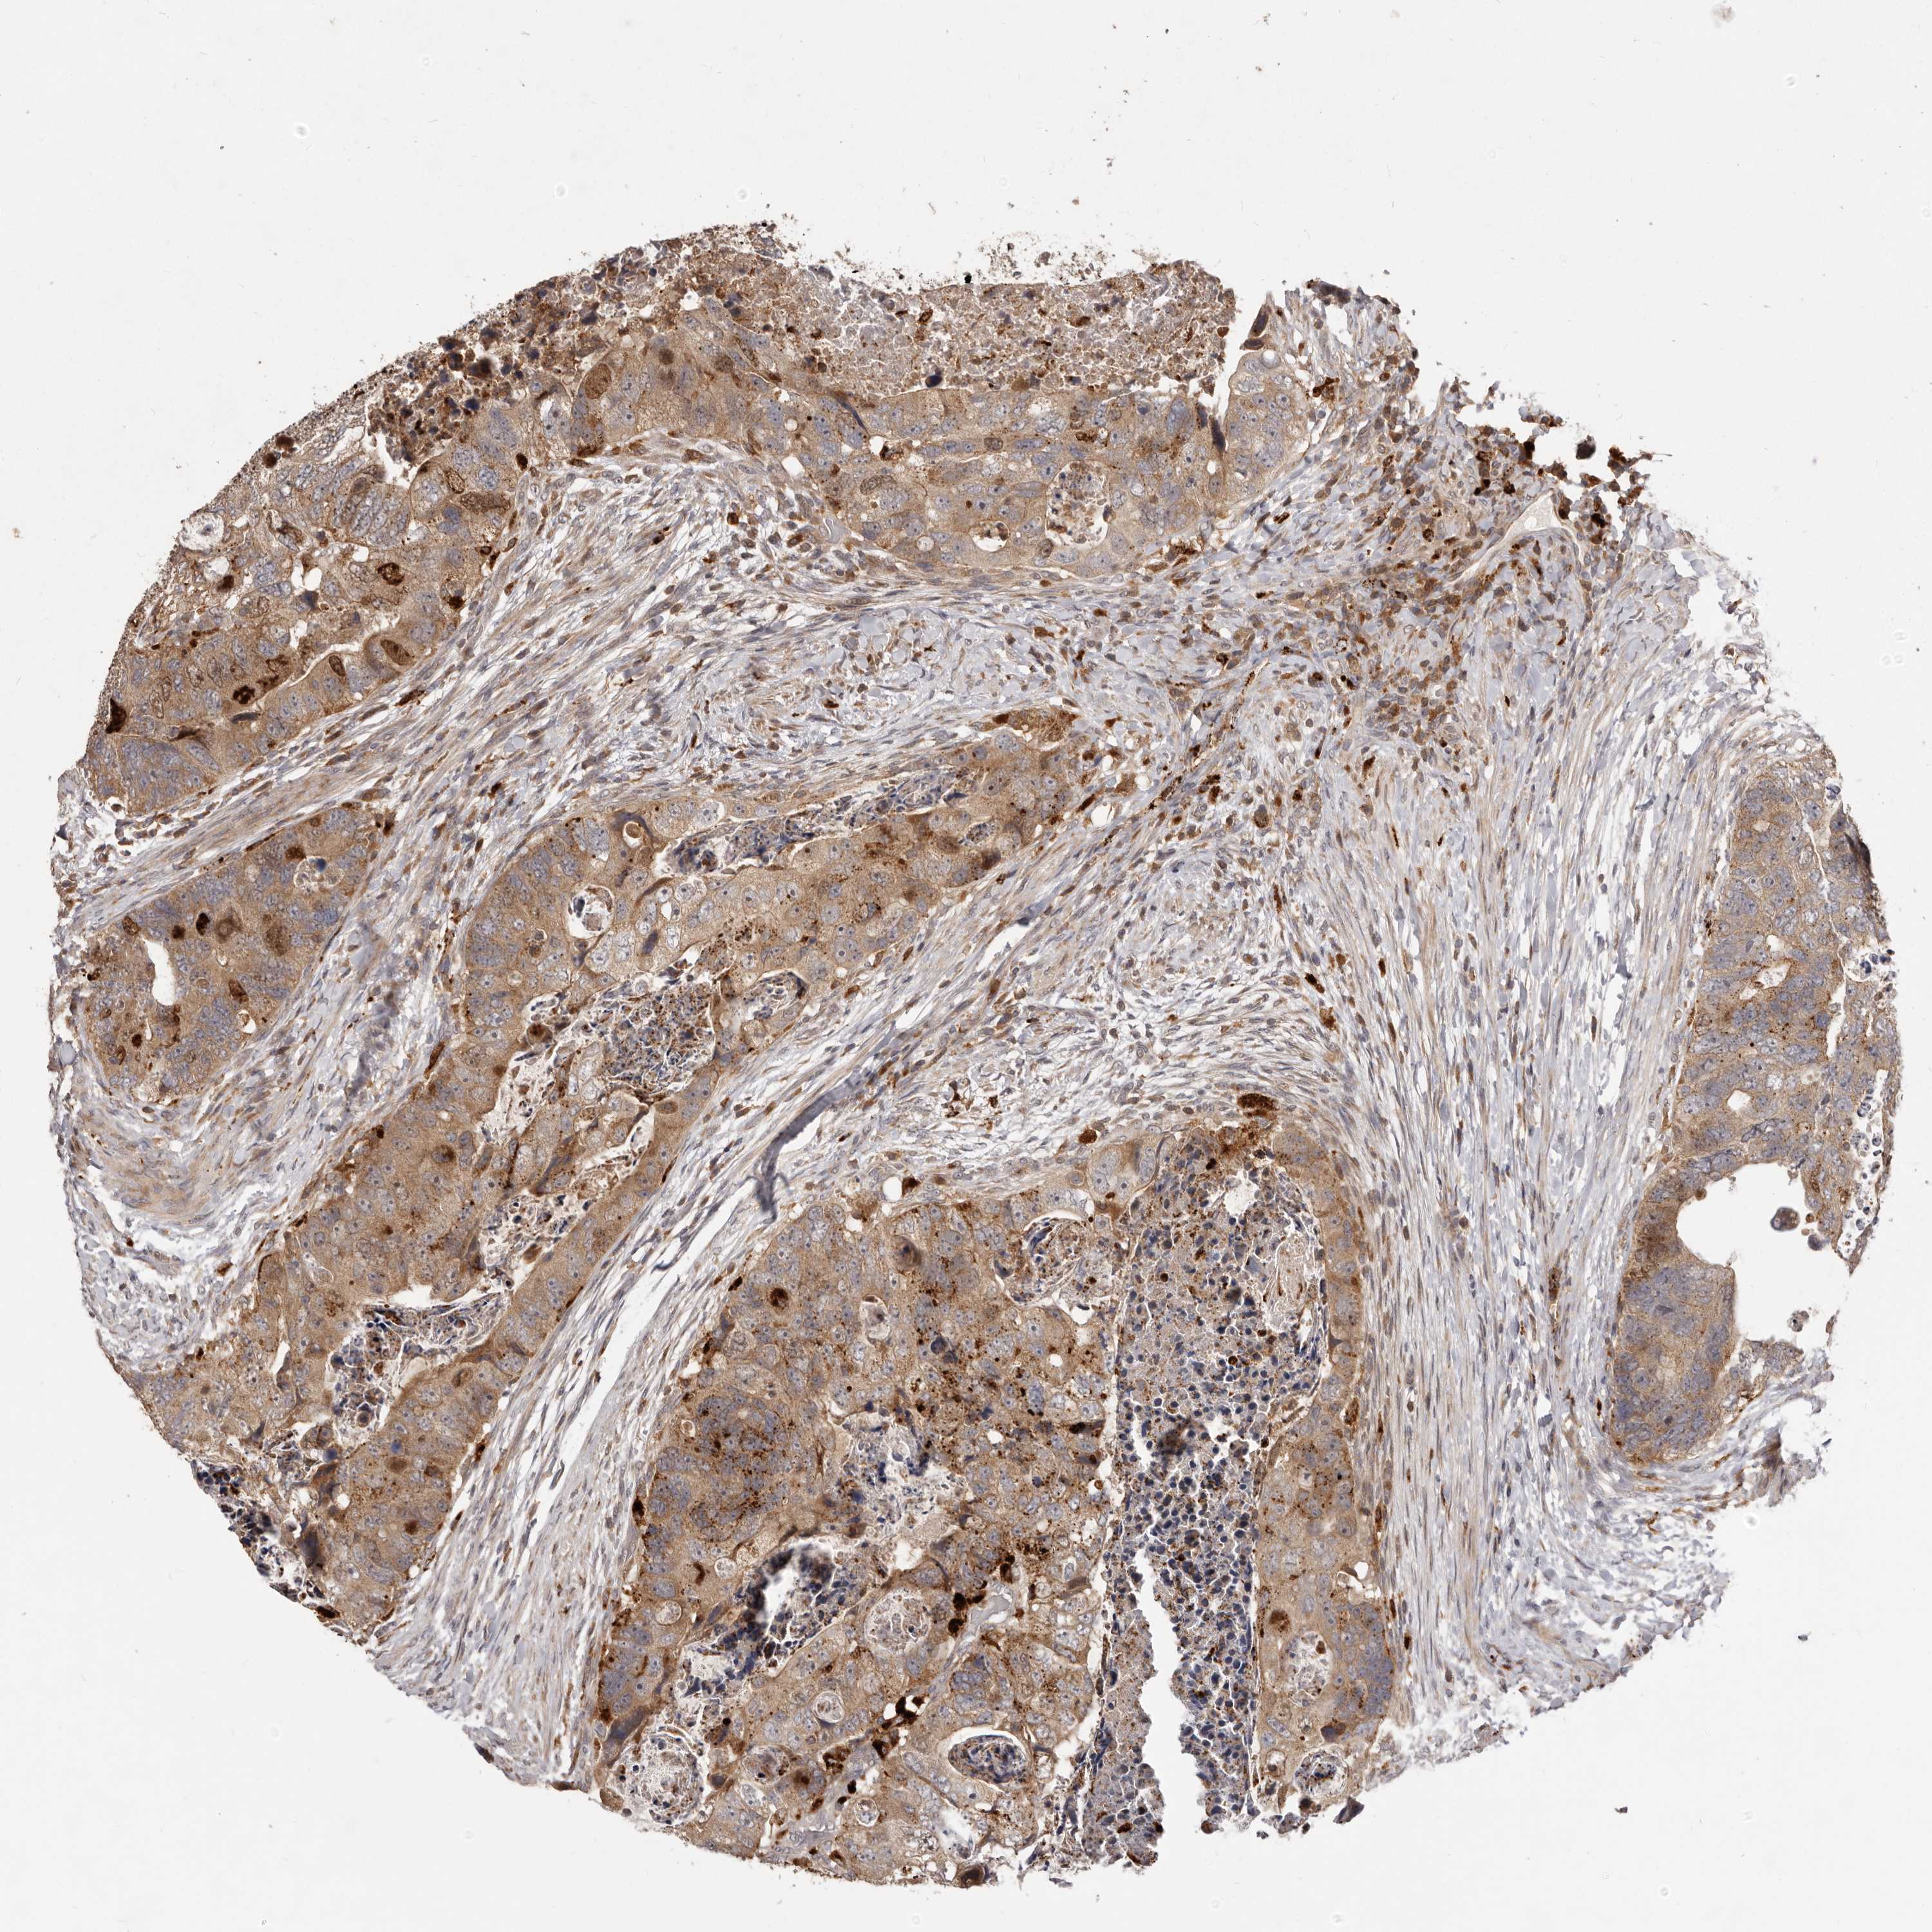

RECTUM ADENOCARCINOMA (TCGA) - Interactive survival scatter ploti

The Survival Scatter plot shows the clinical status (i.e. dead or alive) for all individuals in the patient cohort, based on the same data that underlies the corresponding Kaplan-Meier plots. Patients that are alive at last time for follow-up are shown in blue and patients who have died during the study are shown in red.

The x-axis shows the expression levels (FPKM) of the investigated gene in the tumor tissue at the time of diagnosis. The y-axis shows the follow-up time after diagnosis (years). Both axes are complimented with kernel density curves demonstrating the data density over the axes. The top density plot shows the expression levels (FPKM) distribution among dead (red) and alive patients (blue). The right density plot shows the data density of the survived years of dead patients with high and low expression levels respectively, stratified using the cutoff indicated by the vertical dashed line through the Survival Scatter plot. This cutoff is automatically defined based on the FPKM cutoff that minimizes the p-score. The cutoff can be changed by dragging the vertical line or by entering a cutoff value in the square labeled "Current cut-off".

Under the Survival Scatter plot the p-score landscape (black curve; left axis) is shown together with dead median separation (red curve; right axis). Dead median separation is the difference in median mRNA expression between patients who have died with high and low expression, respectively. It is calculated as follows: median FPKM expression of dead patients with high expression - median FPKM expression of dead patients with low expression. This is intended to aid the user in visually exploring custom cutoffs and the associated p-scores and dead median separation.

Individual patient data is displayed and can be filtered by clicking on one or more of the category buttons on the top of the page. Categories describing expression level and patient information include: high, low, alive, dead, female, male and tumor stages. The scale of the x-axis can be toggled between linear and log-scale by clicking on the "x log" button. Mouse-over function shows TCGA ID, patient information and mRNA expression (FPKM) for each patient.

& Survival analysisi

Kaplan-Meier plots summarize results from analysis of correlation between mRNA expression level and patient survival. Patients were divided based on level of expression into one of the two groups "low" (under cut off) or "high" (over cut off). X-axis shows time for survival (years) and y-axis shows the probability of survival, where 1.0 corresponds to 100 percent.

RNF187 is not prognostic in Rectum Adenocarcinoma (TCGA)

Best expression cut offi

Based on the FPKM value of each gene, patients were classified into two groups and association between prognosis (survival) and gene expression (FPKM) was examined. The best expression cut-off refers the FPKM value that yields maximal difference with regard to survival between the two groups at the lowest log-rank P-value. Best expression cut-off was selected based on survival analysis .

When clicking on this number, the vertical dashed line indicating cut-off, the interactive survival plot, and the Kaplan-Meier curve will be adjusted to show results based on the best expression cut-off.

: 13.37

Median expressioni

Median expression refers to the median FPKM value calculated based on the gene expression (FPKM) data from all patients in this dataset. When clicking on this number, the vertical dashed line indicating cut-off, the interactive survival plot, and the Kaplan-Meier curve will be adjusted to show results based on the median expression.

: N/A

P scorei

Log-rank P value for Kaplan-Meier plot showing results from analysis of correlation between mRNA expression level and patient survival.

N/A

5-year survival highi

5-year survival for patients with higher expression than the expression cutoff.

For melanoma and glioma, 3-year survival is shown.

5-year survival lowi

5-year survival for patients with lower expression than the expression cutoff.

TCGA RNA samplesi

RNA-seq data is reported as average FPKM (number Fragments Per Kilobase of exon per Million reads), generated by the The Cancer Genome Atlas (TCGA) .

Normal distribution across the dataset is visualized with box plots, shown as median and 25th and 75th percentiles. Points are displayed as outliers if they are above or below 1.5 times the interquartile range. FPKM values of the individual samples are presented next to the box plot.

Average pTPM 12.0

Number of samples 88